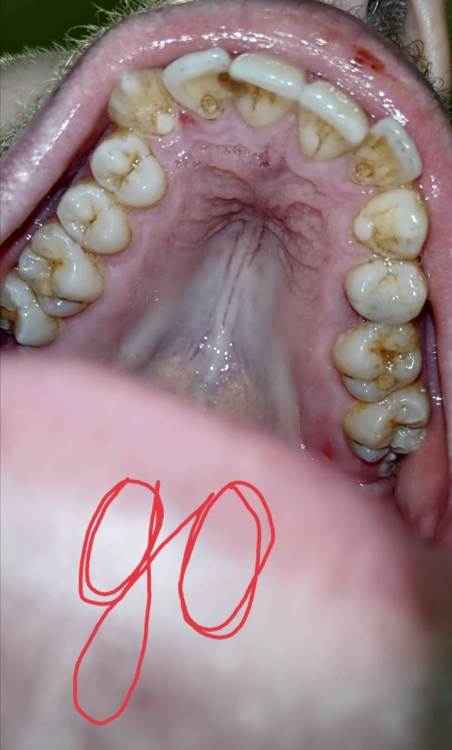

Фотографий много, но приложу три главных: 1) РАНЬШЕ до появления налёта 2) ДО всех процедур очистки 3) ПОСЛЕ всех процедур очистки

Screenshot_20230129_234652.jpg

Screenshot_20230129_234629.jpg